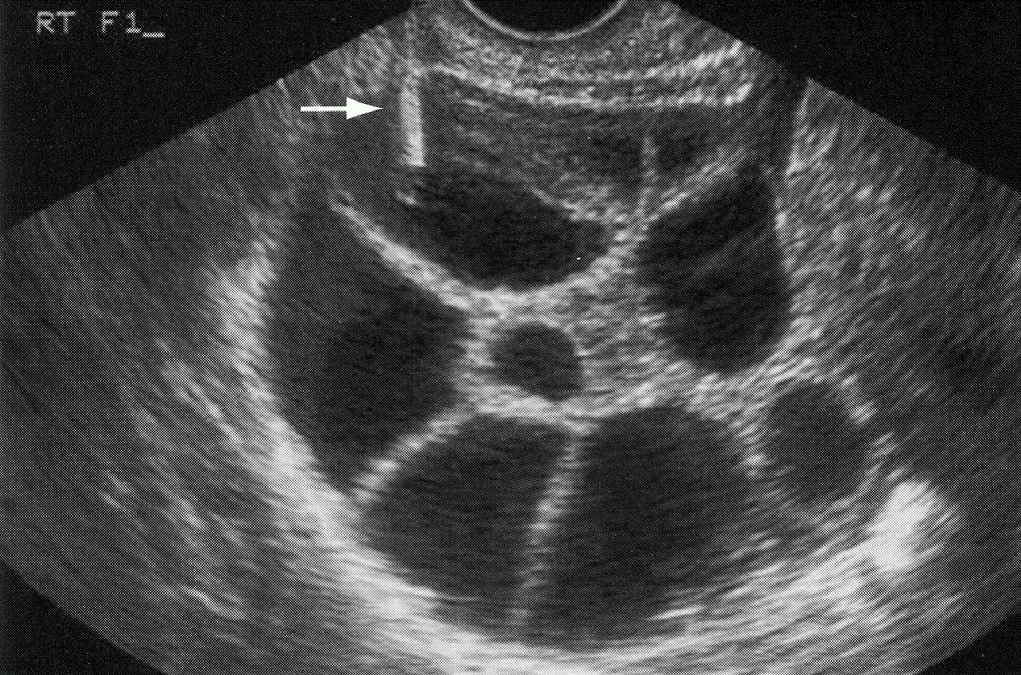

Follicles

Polycystic Ovarian Syndrome“string of pearls”

ovarian volume > 10 cm3